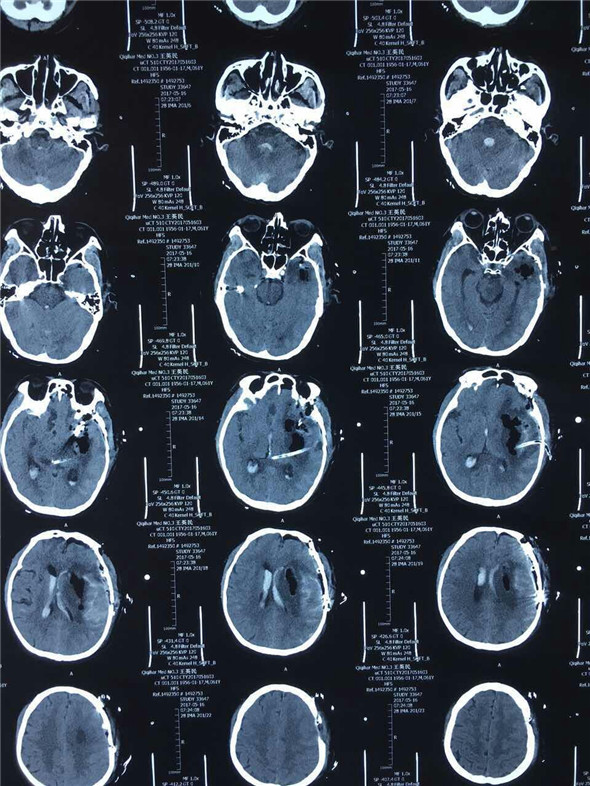

因术前缺少脑256CT及全脑血管选择性造影,动脉瘤的位置、大小情况无从知晓,所以手术切口的设计,术中可能发生的情况的预判,对手术能否成功有着至关重要影响。术中吴主任凭借多年的手术经验及娴熟的手术技巧,仔细而充分的清除颅内血肿,在左侧大脑中动脉M1、M2交界处暴露出动脉瘤,最大直径约1.8cm,2枚动脉瘤夹成功夹闭。经过3个小时紧张而有序的手术,王先生的手术顺利完成。术中将骨瓣成功复位,避免了二次手术,减轻了患者的经济负担,术毕患者双侧瞳孔回复正常,术后第一日患者清醒。

神经外二科自成立以来已多次完成Hunt-HessⅣ-Ⅴ动脉瘤手术,本次快速救治颅内Ⅴ级动脉瘤破裂的成功,从发现患者意识不清到复查头CT,再到转科做好术前准备将患者推进手术室,离不开神经内二科与神经外二科紧密配合。此次默契合作,有力的诠释了珠联璧合,合作无间。为我院脑血管急、重症救治及开辟快捷绿色通道救治抹上浓重一笔。